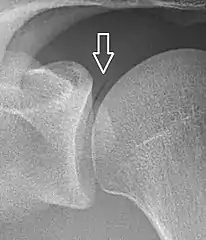

Pneumarthrosis is the presence of air in a joint. Its presentation on radiography is a radiolucent cleft often called a vacuum phenomenon, or vacuum sign.[7] Pneumarthrosis is associated with osteoarthritis and spondylosis.[8]

Pneumarthrosis is a common normal finding in shoulders[7] as well as in sternoclavicular joints.[9] It is believed to be a cause of the sounds of joint cracking.[8] It is also a common normal post-operative finding at least after spinal surgery.[10] Pneumarthrosis is extremely rare in conjunction with fluid or pus in a joint, and its presence can therefore practically exclude infection.[8]

X-ray of a hip with hip replacement and pneumarthrosis, in this case aseptic. A vacuum sign, or vacuum phenomenon, is a normal finding on shoulder X-rays.

A vacuum sign, or vacuum phenomenon, is a normal finding on shoulder X-rays.